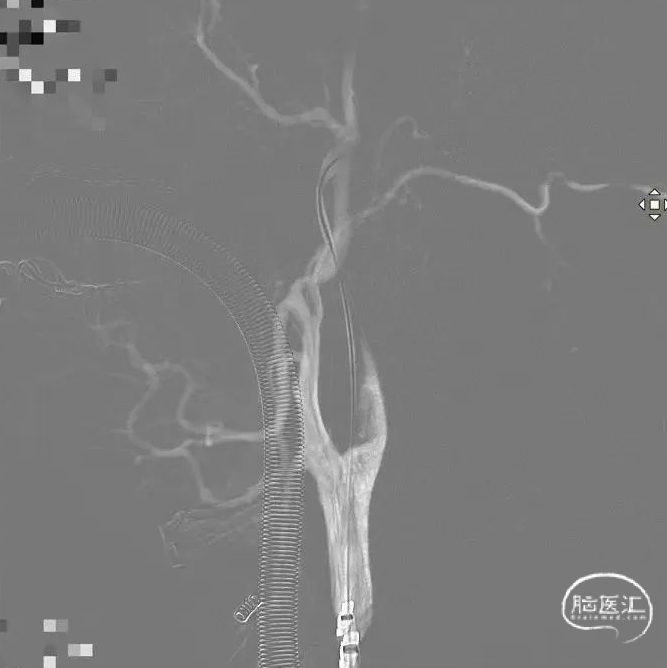

术后DSA影像

正、侧位造影血流复流情况良好,栓子全部取出。